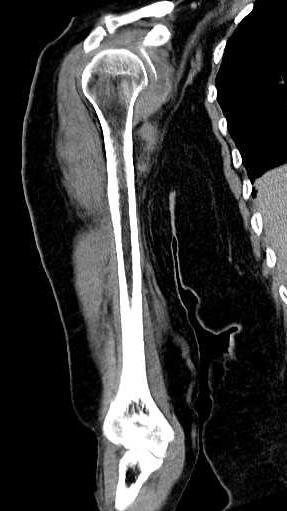

A tomografia computadorizada dos membros é um exame de imagem que serve para auxiliar o médico no diagnóstico de diversas patologias que podem afetar os membros, sendo estes divididos em:

Esse método de estudo é indicado para avaliar alguns sintomas associados aos membros, como dor ou tumefações. Permite também que sejam feitas avaliações das articulações e, sobretudo, análise do componente ósseo. É um excelente método de imagem para observar fraturas e lesões hemorrágicas. Por meio da tomografia, são realizados diagnósticos eficazes e assertivos.